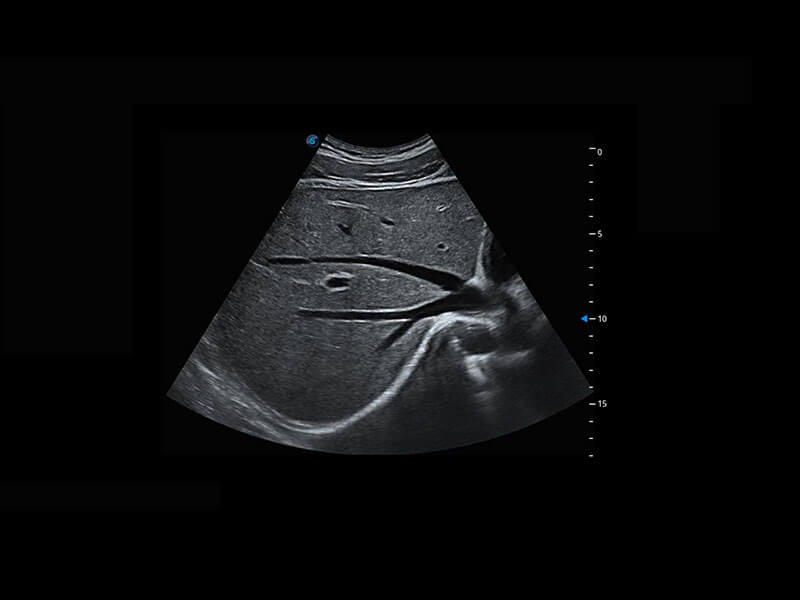

盆底超声

P60为盆底超声检查提供应用方案,多种腔内及腹部容积探头提供从二维、三维到四维的优异图像品质,实时快速三维容积数据获取,专业的测量工具包等人性化设计,为超声医生诊断提供有力保障。

S-Pelvic

能够简化盆底检查的操作流程,可在二维模式及三维成像模式下实现一键自动提取出标准切面、自动识别当前切面、自动测量,提升盆底检查的高效性,同时也能让青年医生快捷的获得准确的检查结果。